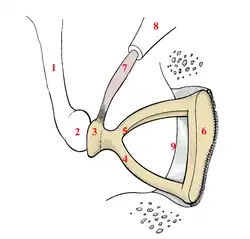

Right-ear stapes

Right-ear stapes -

Stapes: Relative size

Stapes: Relative size